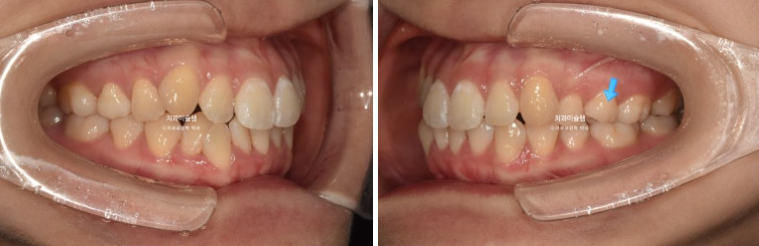

덧니가 보이고 파란화살표에 소구치에 가위교합도 있습니다.

개선된 덧니와 가위교합